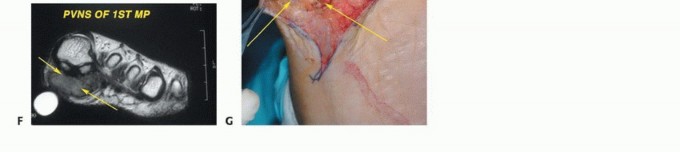

الدراسات التصويرية (Imaging Studies):

- التصوير بالرنين المغناطيسي (MRI): يوفر صورًا مفصلة للغاية للأنسجة الرخوة (العضلات، الأوتار، الأعصاب، الأوعية الدموية) والعظام، مما يساعد على تحديد مدى انتشار الورم بدقة، وعلاقته بالهياكل المحيطة. يعتبر التصوير بالرنين المغناطيسي ضروريًا لتخطيط الجراحة.

أ. الاستئصال الموضعي الواسع (Wide Local Excision):

هو الخيار الأول لمعظم الأورام، خاصة الخبيثة منها في مراحلها المبكرة.

* الهدف: إزالة الورم بالكامل مع هامش أمان من الأنسجة السليمة المحيطة لضمان عدم ترك أي خلايا سرطانية.

* التقنيات المتقدمة: يستخدم الدكتور هطيف تقنيات الجراحة المجهرية (Microsurgery) عند الضرورة، لضمان استئصال دقيق مع الحفاظ على الأوعية الدموية والأعصاب الحيوية. هذا يقلل من تلف الأنسجة السليمة ويحسن النتائج الوظيفية.